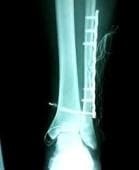

骨折(斜骨折) → プレート&スクリュー固定後

腓骨々幹部骨折のXP画像、転位が大きく、AOプレートで内固定されています。しばしば、脛骨々折を合併することが多く、「脛腓骨骨折」とまとめて診断名がつくことがあります。